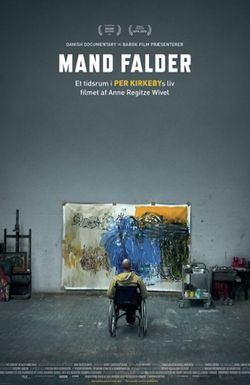

The film follows an artist's courageous and humorous response to a death sentence, as he battles ALS. Despite the degenerative condition, he adapts his painting techniques, switching from right to left hand, and then both hands held at his waist. With determination, he creates over 100 portraits in just four months.

Imber's Left Hand

An artist's courageous and uplifting story unfolds as he copes with an ALS diagnosis, transforming his challenges into opportunities for innovative expression.